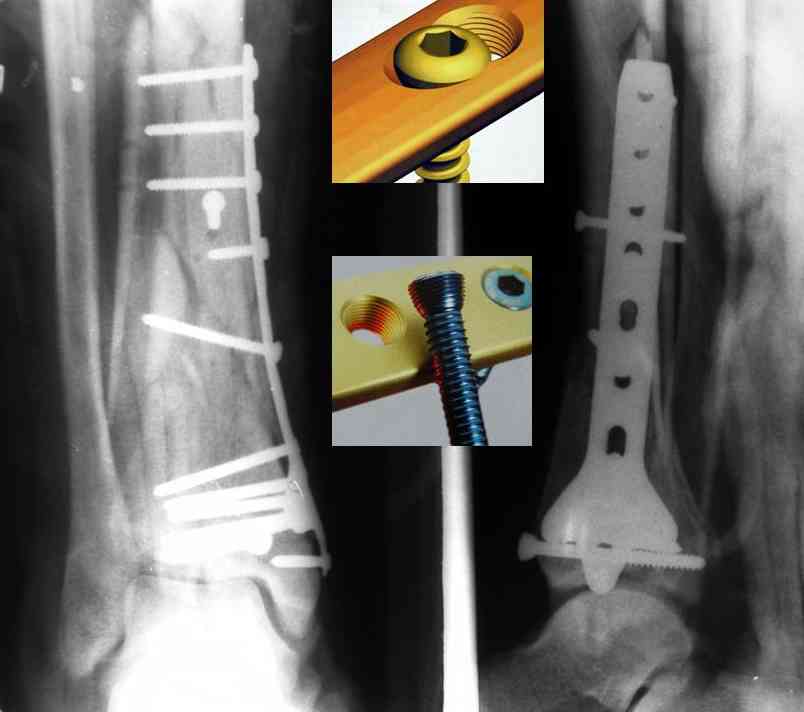

На рентгенограммах типичный перелом пилона по типу С-3. есть опыт до 100 открытых опреаций у нас в клинике. 20 примерно в год. Принцип один -все внутрисуставные переломы нуждаются в открытой репозиции и внутренней стабильной фиксации. При поступлении КТ не надо, так как получается только нагромождение костей. Истинной картины нет. Главное восстановить длину малоберцовой кости - это ключ к успеху. При поступлении меньше всего надо думать о сосудистых расстройствах, т.к. сама операция и репозиция даже сначала частичная даёт улучшение сосудитых нарушений. Причём очень быстро. Операция в 2этапа. При поступлении доступ позади наружной лодыжки, причём обязательно. После этого репозиция малоберцовой кости и фиксация пластиной 1/3 трубки под винт 3,5. Дренаж и любой аппарат наружной фиксации. Затем после спадения отёка на 5-7-10 день аппрат снимается и дугообразный разрез спереди от медиальной лодыжки 10-12 см. Главной чтобы расстояние между 1 и вторым разрезом было не меньше 7-8 см. Тогда не будет некрозов лоскутов. Таранная кость используется как матрица на неё укладываются отломки и фиксируются пицами. Ренг-контроль. Отломки лежат все отдельно, но ничего не высыпется. При переломах С-3 всегда нужна костная пластика (из крыла). Фиксация пластиной лист клевера простой или LCP. Гипс не нужен. Дренаж до 48 часов. Операция длится 3-4 часа обязательно без жгута. Посылаю примерно такой же случай.

Послала ещё два снимка, если не пройдут, пошлю ещё. Дрягин. Если есть вопросы, готов ответить.

Кстати, при переломах переднего края по классификации АО В-3 при переломах пилона пластина укладывается по передней поверхности. Она достаточно тонкая и эластичная, не надо этого бояться. Посылаю три снимка.